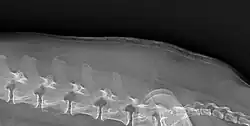

Cutaneous atrophy in a dog with Cushing's

Cushing's may cause a breakdown of dermal proteins, causing shiny and thin skin, this can lead to secondary infection and is pathognomonic of Cushing's.[2]